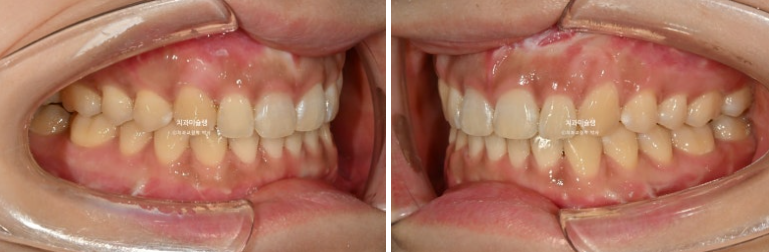

25.02~25.10

중심선은 정확히 맞으며

어금니 교합은 물샐틈 없는 1급 교합관계를 보입니다.

교합은 좋은편이며

배열도 거의 완성이 되었습니다.